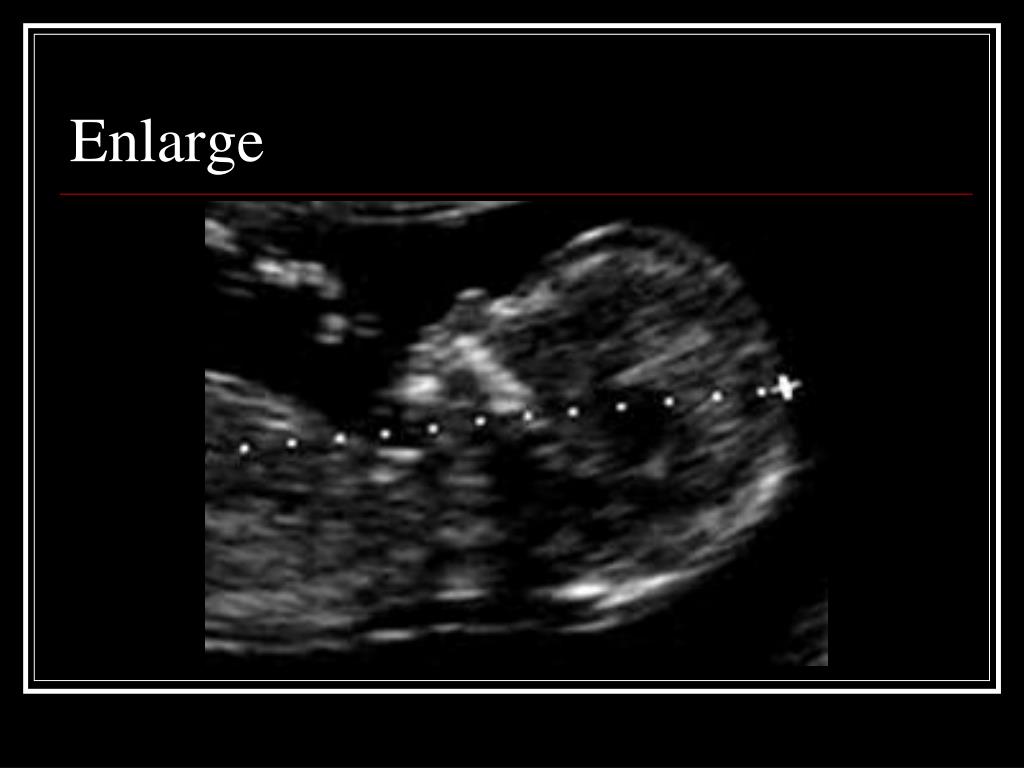

15. Enlarge

16. Caliper Placement